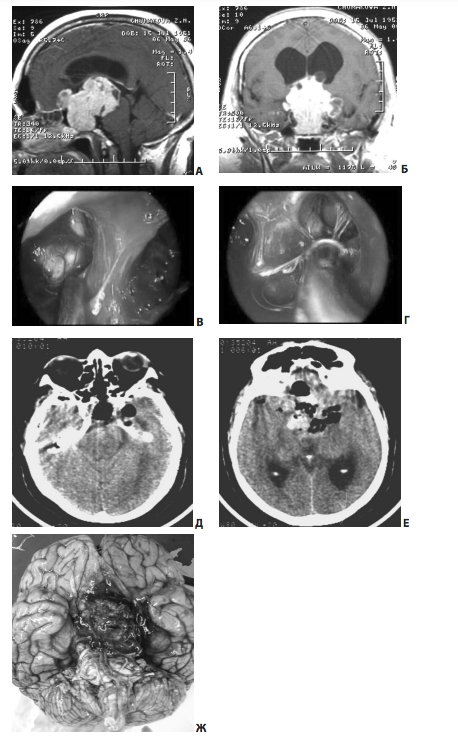

На рис. 11 представлен пример удаления гигантской эндо-супра-латероселлярной аденомы гипофиза — от задне-верхних отделов левого кавернозного синуса формировался крупный вырост опухоли с признаками старого кровоизлияния в него

Рис. 11. Пример удаления гигантской эндо-супра-латероселлярной аденомы: А, Б — КТ до операции; В, Г — МРТ до операции, Д, Е — МРТ через несколько месяцев после операции

Первым этапом была удалена эндо-супраселлярная часть опухоли под контролем 0 и 30-градусных эндоскопов. Затем под контролем 45º и 70º эндоскопов опухоль удалена из полости левого кавернозного синуса, в задних отделах синуса обнаружен вторичный узел опухоли, из его полости выделилось некоторое количество темно-бурой жидкости, после чего со стенок вторичного узла удалено небольшое количество опухоли (рис. 11, 12). При контрольной МРТ через несколько месяцев после операции явные остатки опухоли, в том числе и в полости кавернозного синуса, не определяются. Стрелкой указана складка капсулы удаленного вторичного узла.На рис. 13 представлен пример удаления большой эндо-супра-латероселлярной аденомы гипофиза. Однако, по данным контрольной КТ в первые сутки после операции, можно лишь сказать, что нами была удалена большая часть опухоли, но судить о том, есть ли остатки аденомы и какого они размера, достаточно сложно.

Рис. 12. Интраоперационный снимок этапа удаления гигантской эндо-супра-латероселлярной аденомы (45º эндоскоп): 1 — проекция левого зрительного нерва; 2 — капсула супраселлярного отдела опухоли; 3 — задне-верхние отделы левого кавернозного синуса

Рис. 13. Пример субтотального (?) удаления большой эндо-супра-латероселлярной аденомы гипофиза: А, Б, В — МРТ до операции; Г, Д — КТ в первые сутки после операции

Рис. 14. Пример частичного (?) удаления большой эндо-супра-латероселлярной аденомы гипофиза: А — МРТ до операции; Б — КТ на вторые сутки после операции — в полости вторичного узла кровь, гемостатические материалы, остатки опухоли; оценить радикальность проведенной операции по данным КТ сложно

По данным контрольной КТ, произведенной не сразу после операции, достаточно сложно судить о радикальности проведенной операции — в образовавшейся полости скапливается кровь, кровью пропитываются гемостатические материалы, имбибируются остатки опухоли (рис. 14, Б).